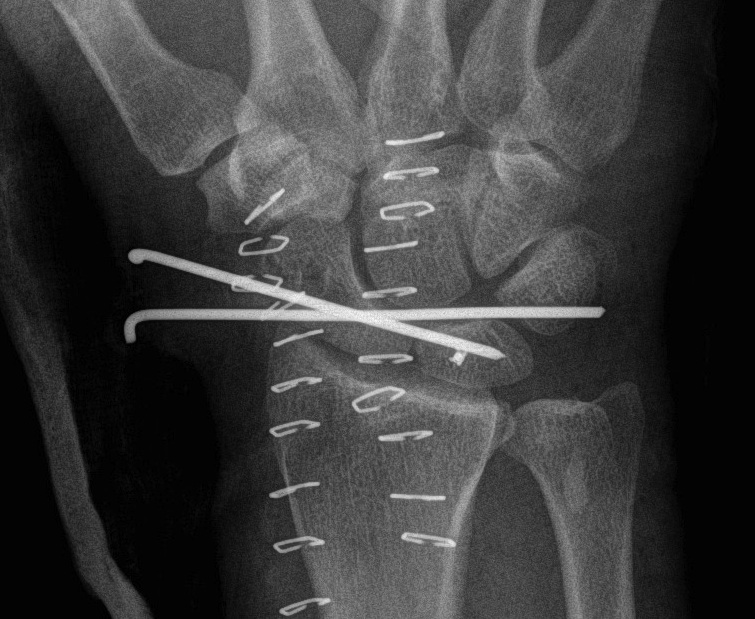

1. No scaphoid fracture

Reduce lunate

- closed reduction

- open reduction

Dorsal approach

- longitudinal incision

- 3/4 extensor compartment

- mobilise EPL laterally

- open dorsal between DRC and DIC ligaments

- joysticks in scaphoid and lunate

- reduce DISI deformity

- K wires SC / SL / LT (areas of ligament rupture)

- repair SL ligament back onto scaphoid with anchors / transosseous sutures

- ORIF any capitate fractures

- repair LT ligament + augment with capsule

+/- Volar approach

- difficulties reducing lunate

- perform CTD

- repair rent in volar capsule / Space of Poirier

Recent trends

- add SL screw

- add Blatt capsulodesis

- repair rent in volar capsule

- make wrist as stiff as possible to prevent late OA